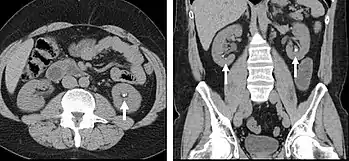

Detection and characterization of renal parenchymal masses is a frequent indication for CT. An initial noncontrast CT is important for detecting calcium or fat in a lesion, and to provide baseline attenuation of any renal masses. Following noncontrast scanning, intravenous contrast is injected and a corticomedullary phase is obtained at approximately 70 seconds (figure 7a, 7b). The corticomedullary phase is characterized by enhancement of the renal cortex as well as the renal vasculature. This phase is valuable in the evaluation of benign renal variants, lymphadenopathy and vasculature, however certain medullary renal masses may not be visible during this phase due to minimal enhancement of the medulla and collecting system. The parenchymal phase is obtained approximately 100–200 seconds after the injection of contrast material (figure 7c). Parenchymal phase imaging demonstrates continued enhancement of the cortex, enhancement of the medulla, and various levels of contrast material in the collecting system. The parenchymal phase is highly important for the detection and characterization of renal masses, parenchymal abnormalities, and the renal collecting system. This method of imaging does not evaluate for abnormalities of the collecting system.

Common renal masses can occasionally be differentiated from each other using this imaging technique. Renal cell carcinomas and oncocytomas typically demonstrate intense heterogeneous enhancement on the parenchymal phase images and cannot be reliably differentiated from each other but can be distinguished from other renal masses. Angiomyolipomas (AML’s) also demonstrate intense contrast enhancement but characteristically contain macroscopic fat which can be detected on the noncontrast images, and can help to differentiate AML’s from renal cell carcinomas and oncocytomas. Renal lymphoma on the other hand, will often have decreased enhancement when compared to the renal parenchyma on the parenchymal phase images.

- FIGURE 7. Selected images from a renal mass specific protocol CT. Corticomedullary phase (axial 7a) demonstrates peripheral enhancement of the renal cortex with minimal opacification of the renal medulla. There is a large renal cell carcinoma in the left kidney (right in image) which can be differentiated from the normal renal parenchyma by the heterogeneous and differential enhancement. The renal artery and vein are opacified in this phase as well. The collecting system is not opacified (coronal reformat 7b). In the parenchymal phase, the renal cortex and the medulla are enhancing. The renal cell carcinoma in the left kidney is not as well defined when compared to the corticomedullary phase images, but is actually slightly more conspicuous. There is some contrast noted within the collecting system during this phase (7c).